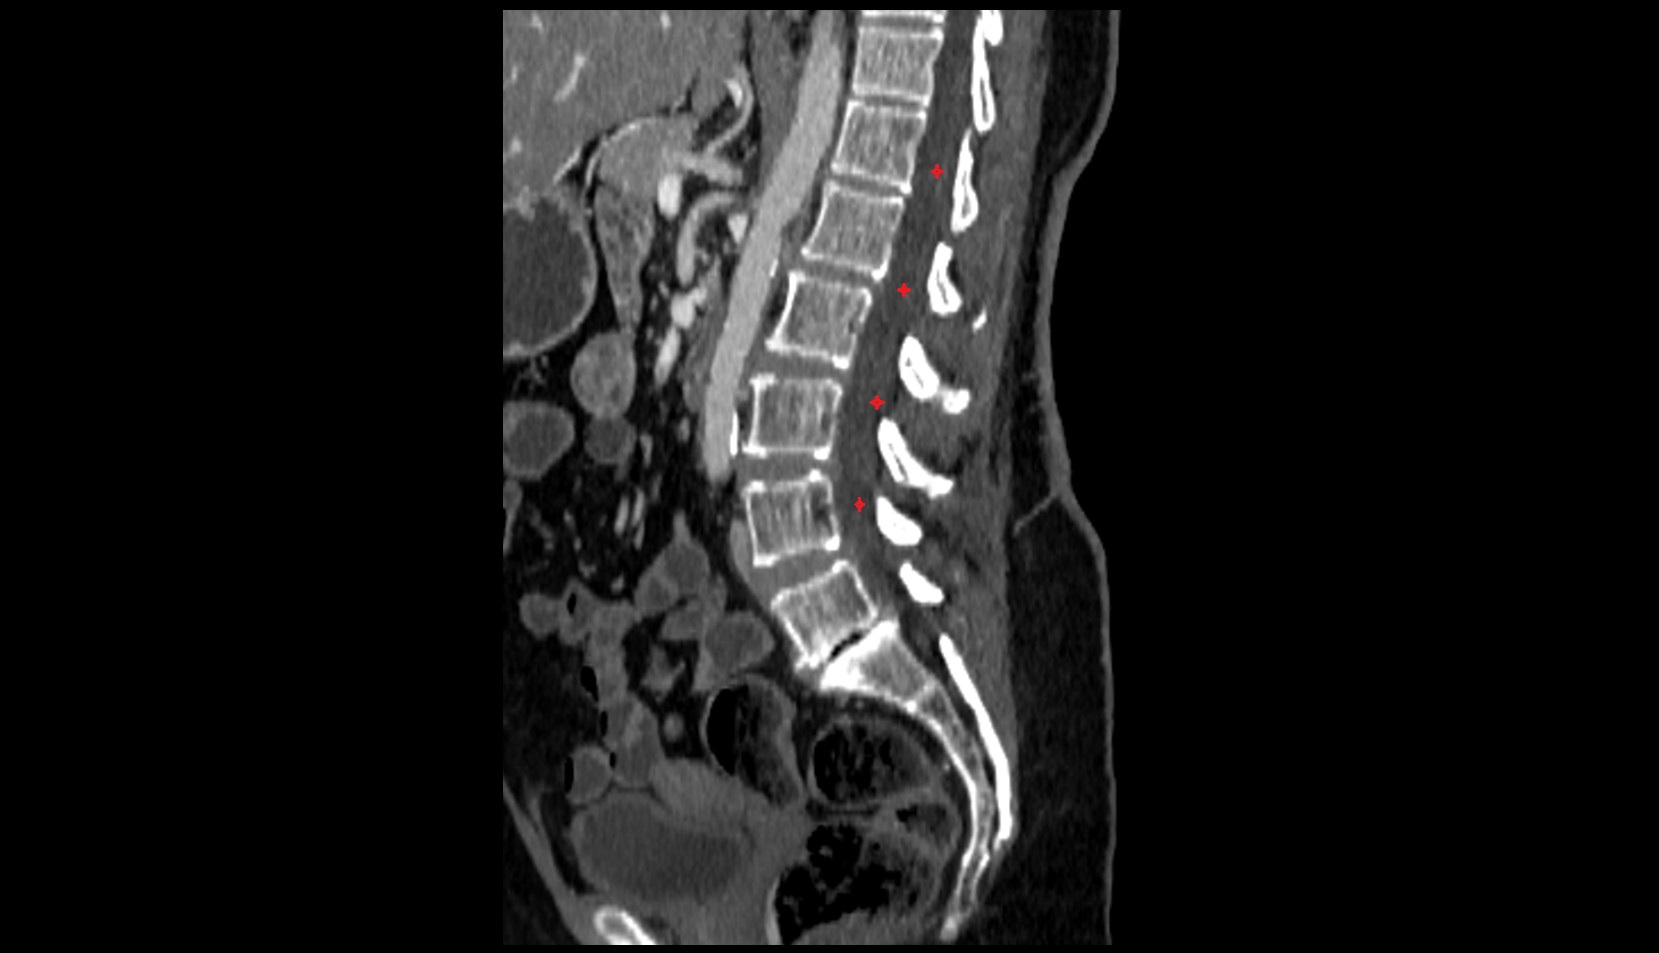

- L5–S1 Intervertebral disc

- L4–L5 Intervertebral Disc

- L3–L4 Intervertebral Disc

- L2–L3 Intervertebral Disc

- L1–L2 Intervertebral Disc

- T12–L1 Intervertebral Disc

- Abdominal aorta

- Aortic bifurcation